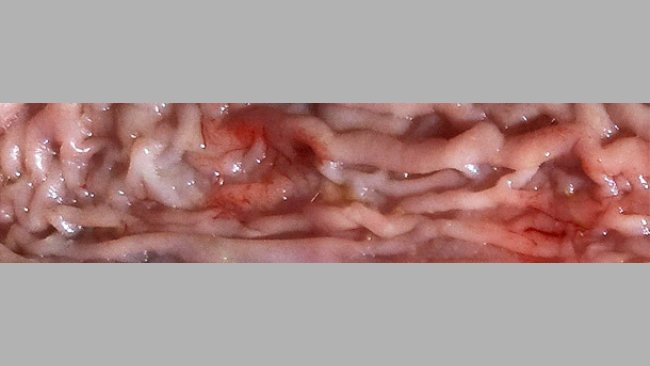

La ileitis tiene distintas formas de presentación, incluso en el mismo cebadero, y resulta frecuente que coincidan la forma subclínica con una presentación más aguda y grave.